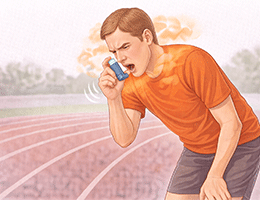

천식 (호흡기계 (기관지, 폐))

기관지천식 (Bronchial Asthma)

운동유발천식 (Exercise-induced Asthma)